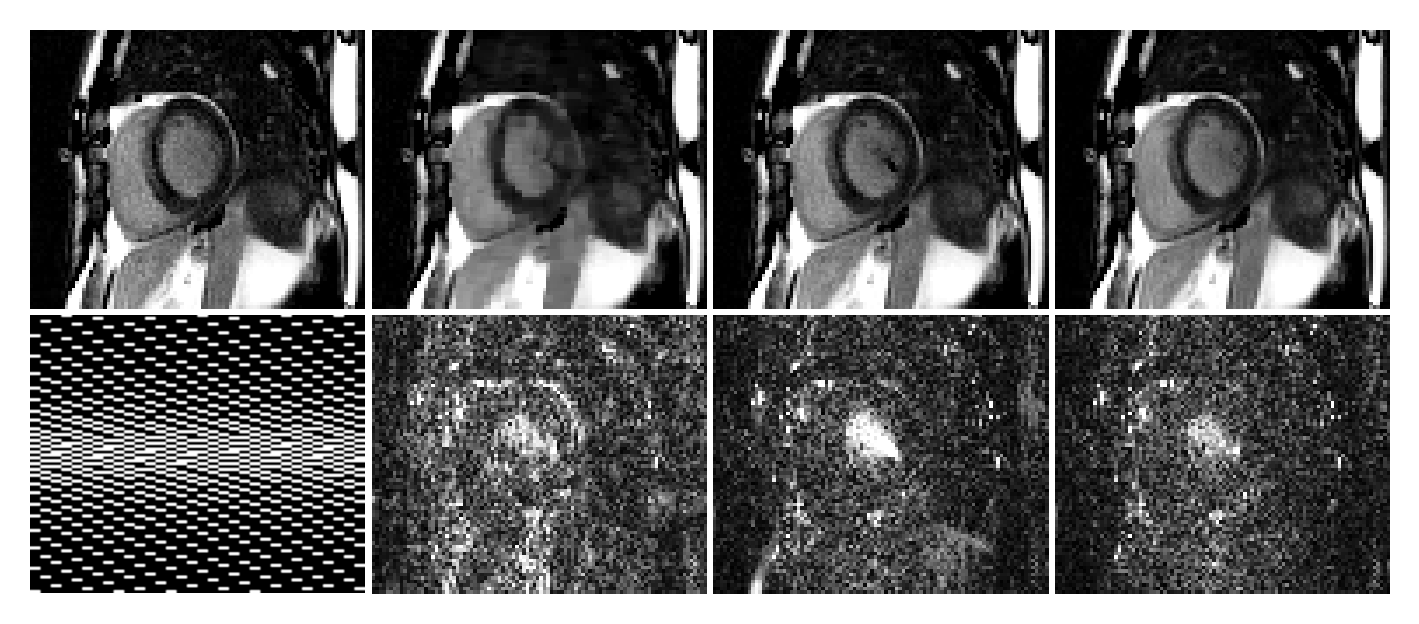

Refer to caption

TrueCSL+SDISCUS

Fig.ย 4: Top row: A representative frame from one of the patients at R=4๐‘…4R=4. Bottom row: sampling mask (frames: left-right, phase-encoding: top-bottom, frequency-encoding: not shown) and ร—5absent5\times 5 error maps.

Tableย 3 compares DISCUS with CS and L+S at three different acceleration rates. In terms of NMSE, DISCUS offers a significant advantage over CS and L+S at all three acceleration rates, while L+S marginally outperforms DISCUS in terms of SSIM. Fig.ย 4 shows a representative frame from one of the image series at R=4๐‘…4R=4. In this example, DISCUS is able to preserve fine details, while CS shows excessive smoothing and blocky artifacts and L+S shows a significant artifact inside the left ventricle, as highlighted by red arrows.